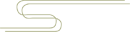

腰椎间盘突出症是因腰椎间盘变性、纤维环破裂,髓核组织突出压迫和刺激神经根、马尾神经所引起的一种综合征,是导致腰腿痛最常见的原因之一。

腰椎间盘突出症常发生于青、中年,好发部位为 L4-5、L5-S1,占 90% 以上。腰椎间盘突出症发病的基础是椎间盘的退行性变,腰部外伤或工作、生活中反复的轻微损伤导致髓核突出产生症状。